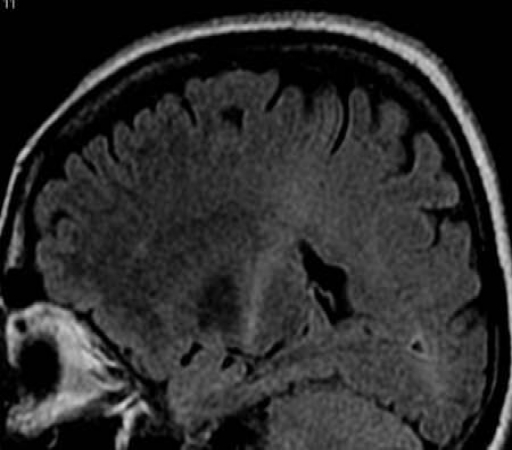

مطالعات محققان آمریکایی نشان می دهد ژن درمانی بهترین روش درمان بیماری عصبی ALS است. از مدیکال اکسپرس، بیماری ALS (اسکلروز آمیوتروفیک جانبی) که بیماری لوگرینگ نیز نامیده می شود، یک بیماری عصبی پیشرونده است که سبب زوال تدریجی سلول های عصبی می شود و توانایی حرکتی بیمار را سلب می کند. در ALS بیمار به مرور زمان توانایی مکالمه را از دست می دهد...نظرات ارزشمند شما